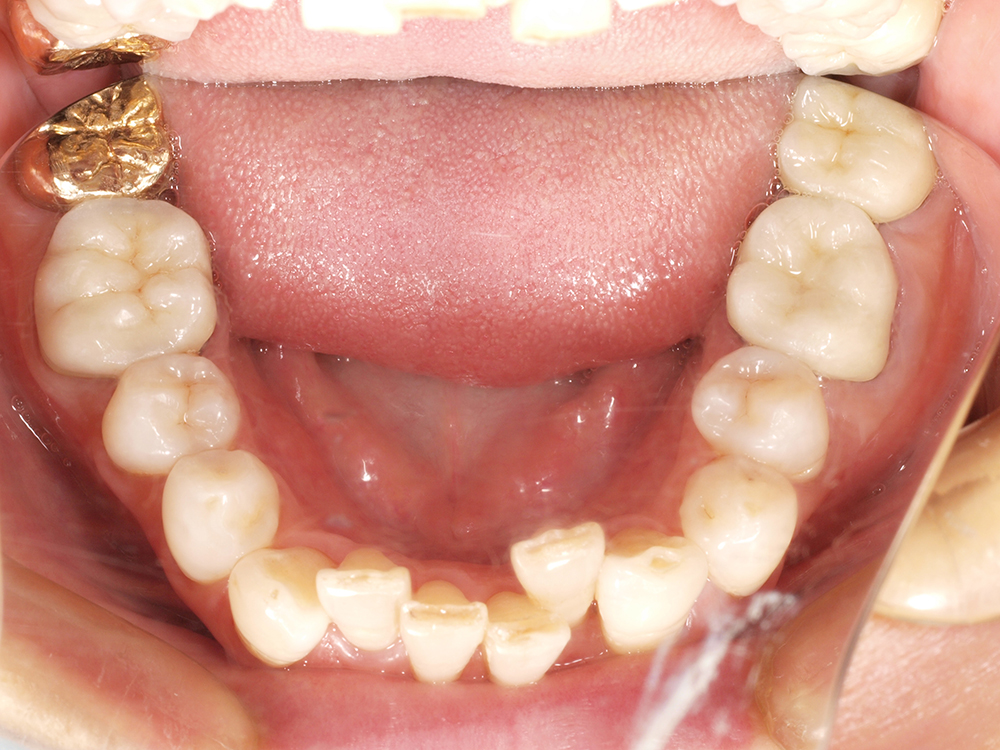

53歳 男性

- 主訴

- 全然噛めない。上の歯が取れてきた

- 処置内容

- 上顎:8本 下顎:2本

- 治療費用

- 上顎:約320万円(税込)、下顎:約160万円(税込)

- 治療期間

-

上顎:1年(仮歯まで8か月)

下顎:8か月(仮歯まで5か月)

- リスク

- 上部構造物、仮歯の破折、術後の腫れ(3日)、人工歯根脱落リスクがあります